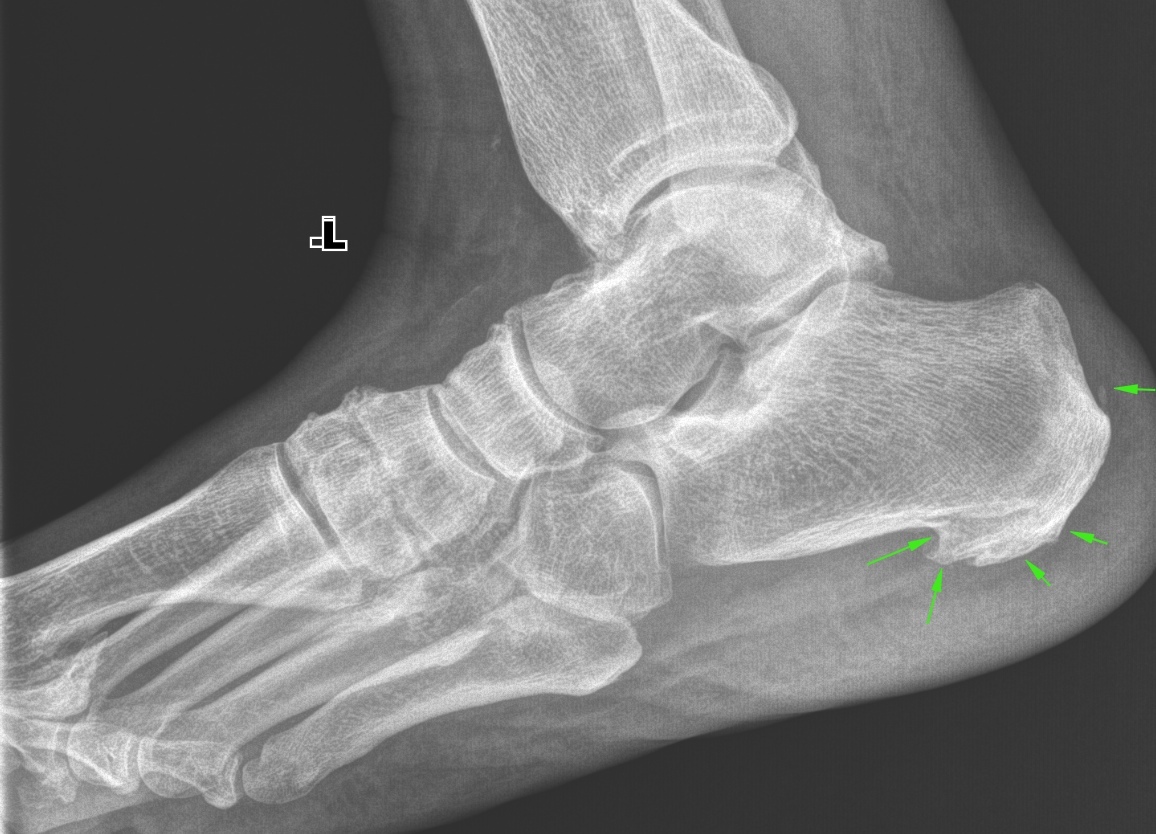

Анатомические фото голеностопного сустава и его суставных поверхностей